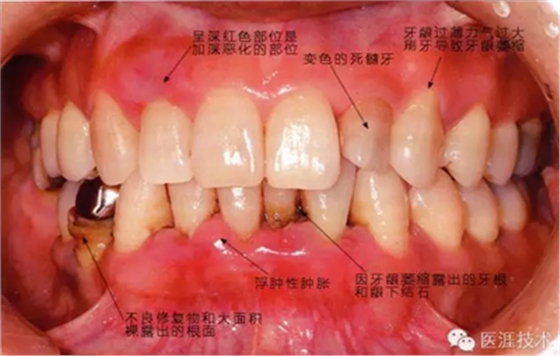

患有牙周病的牙周組織的臨床照片

56歲牙周炎男性的臨床照片

正在服用高血壓藥中的56歲男性。菌斑控制得不好。通過(guò)牙周探診,全頜有4~6mm的牙周袋,在X光片中可以看到全頜中度牙槽骨吸收,磨牙處一個(gè)地方是重度牙槽骨吸收。通過(guò)比較牙周病進(jìn)展?fàn)顟B(tài),邊緣部有大范圍浮腫(發(fā)紅、腫脹),和纖維性肥厚。這也可能是服用中的降壓藥的副作用導(dǎo)致的。因?yàn)檠例l、牙槽骨比較厚,牙齦呈架子狀。